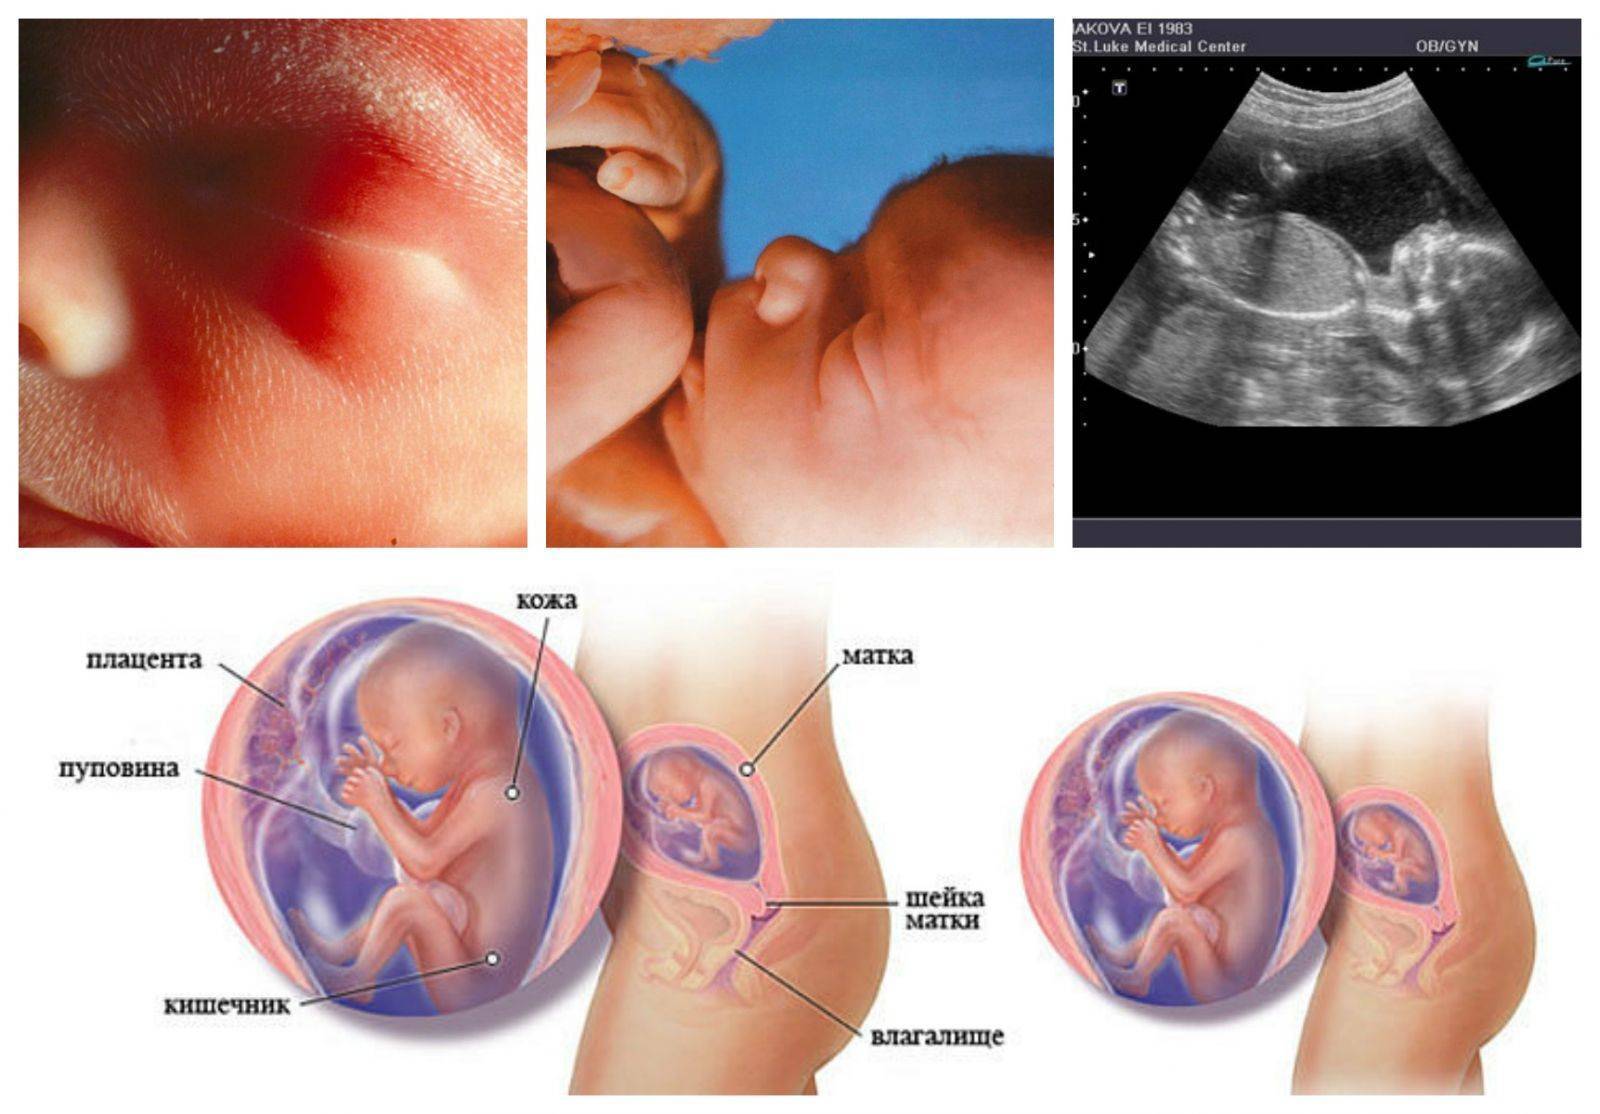

Важный этап: развитие малыша на 20-й неделе беременности

Раздел: Снимки-откровения